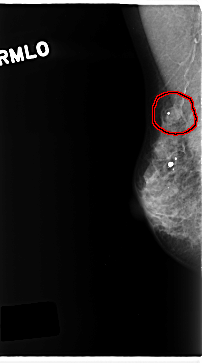

C_0221_1.RIGHT_MLO

RIGHT_MLO LINES 4712 PIXELS_PER_LINE 2616 BITS_PER_PIXEL 12 RESOLUTION 50 OVERLAY

FILE: C_0221_1.RIGHT_MLO.OVERLAY

TOTAL_ABNORMALITIES 1

ABNORMALITY 1

LESION_TYPE MASS SHAPE OVAL MARGINS CIRCUMSCRIBED

ASSESSMENT 4

SUBTLETY 4

PATHOLOGY MALIGNANT

TOTAL_OUTLINES 1

BOUNDARY